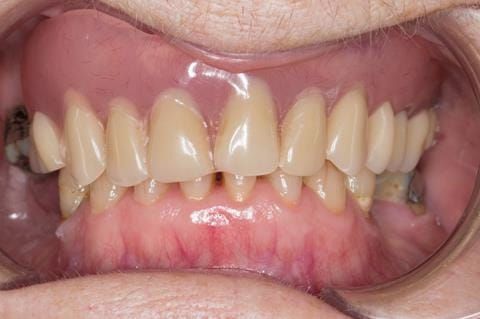

- Poorly fitting cobalt chromium based maxillary partial denture, which has been added to. This exhibited poor retention, stability and tissue fit (support). Unable to wear a new acrylic based denture.

- Eight mandibular anterior teeth worn incisal edges from now extracted maxillary anterior crowns. Gingivitis - owing to inadequate oral hygiene.

- Bruxism.